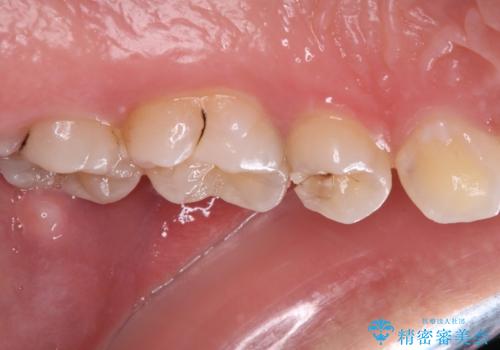

- 食事の度に物が挟まるとのことで来院された患者様です。

目視でも欠損が認められ、レントゲン写真からもむし歯が認められる状態でした。

患者様と相談の上、セラミックインレーで精密な修復治療を行うこととしました。